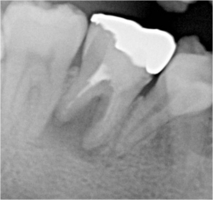

術前 ➡

術中

根の先に影(感染)が出てしまい根の治療を行わないといけないのですが以前他院にて処置を施した古い薬が入っています

画像を見ると手前の根にはしっかりと先まで薬が入っていません(1枚目の画像)